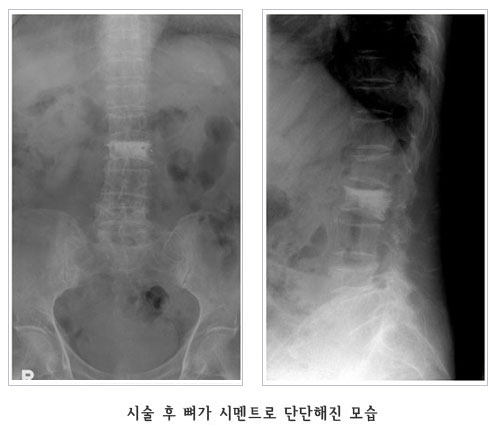

°æÇÇÀû ôÃß¼ºÇü¼ú (Vertebroplasty)

°ñ´Ù°øÁõ¼º ôÃ߾йڰñÀý¿¡¼­ ¼ö¼úºÎÀ§¸¦ ±¹¼Ò ¸¶ÃëÇÑ ÈÄ X-¼± Åõ½Ã±â·Î Åõ½ÃÇϸ鼭, °ñ ½Ã¸àÆ®¸¦ °ñÀýµÈ ºÎºÐ¿¡ ÁÖÀÔÇÏ¿© ôÃß»À ÀÚü¸¦ ưưÇÏ°Ô º¸°­½Ãŵ´Ï´Ù.